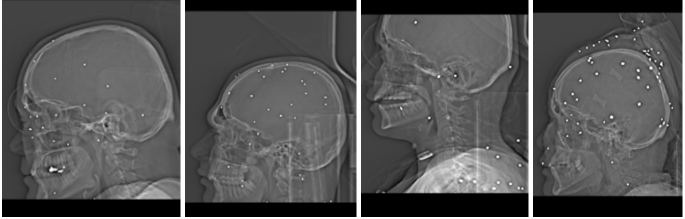

۱) جراحت در سر، صورت، چشم و گردن

در توصیفهای پزشکان، بیشترین بار «خطر نابینایی» و «خطر آسیب مغزی» در آسیبهای سر، صورت و ناحیه اوربیت دیده میشود. در چند مورد، پزشک بهطور مشخص از وجود ساچمهها در صورت و اطراف کاسه چشم، احتمال ورود از مسیر صورت، آسیب مستقیم کره چشم یا اوربیت و «احتمال بالای نابینایی دائمی» سخن میگوید.

الگوی ساچمهای با درگیری چشم و جمجمه و ریسک بالای مرگ

در برخی پروندهها، علاوه بر خطر بینایی، به احتمال حضور ساچمهها در مغز یا نزدیک ساختارهای حیاتی جمجمه اشاره شده که ماهیتا میتواند تهدیدکننده حیات باشد یا در صورت بقا به ناتوانی پایدار ذهنی و جسمی بینجامد. در چند تصویر، نشانههایی مانند گاز قابل توجه زیر جمجمه یا فشار بر مغز، بهعنوان یافته بحرانی و پرخطر توصیف شده است.

در توصیفهای پزشکان، الگوی تکرارشونده شامل پراکندگی متعدد ساچمه در سر و صورت، اطراف اوربیت، گردن و اندامهاست. موارد متعددی از آسیب چشمی با خطر نابینایی دائمی ذکر شده و در برخی پروندهها، ساچمهها در سینوسها، قاعده جمجمه یا مجاورت ستون فقرات گردنی مشاهده شدهاند. در چند مورد، علاوه بر آسیب نرمبافتی گسترده، احتمال درگیری عروق بزرگ یا خطر خونریزی شدید مطرح شده است. در آسیبهای سر و گردن، برخی ارزیابیها بهصراحت به ریسک بالای مرگ یا پیامدهای عصبی پایدار اشاره کردهاند؛ بهویژه زمانی که تراکم ساچمهها در یک ناحیه محدود و حیاتی بالا بوده است.

در مواردی که با شلیک نزدیک یا نیمهنزدیک سازگار است، تصاویر نشاندهنده تجمع متراکم ساچمهها در یک میدان محدود آناتومیک است؛ الگویی که با انتقال انرژی بالا به بافت و تخریب شدید نرمبافت یا حتی خردشدگی استخوان همراه بوده است. در مقابل، در برخی آسیبهای اندام تحتانی، ساچمههای متعدد در اطراف زانو یا ران بدون شکستگی واضح استخوان مشاهده شدهاند، اما همچنان با خطر آسیب عروق و اعصاب و پیامدهای عملکردی بلندمدت همراه بودهاند.